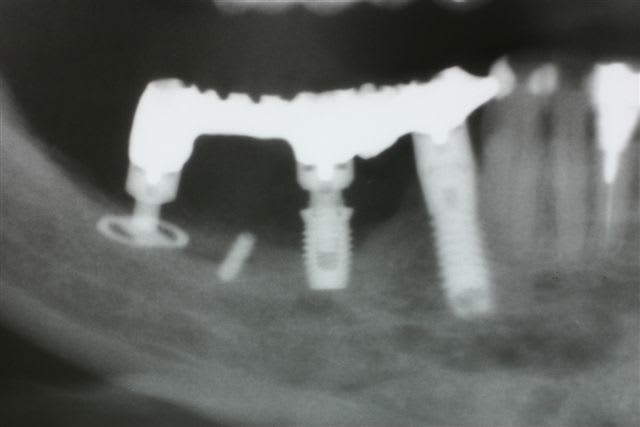

3 Radiographie Panoramique de la correction

4 Utilisation d'un implant à plaque.

La vis d'ostéosyntèse impossible à dévisser a dû être coupée.